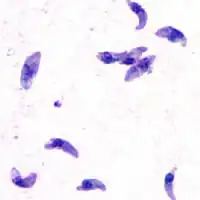

Die Apicomplexa (von lat. apex ‚Spitze‘) sind einzellige, zu den Eukaryoten gehörige Parasiten, die infektiöse Sporozysten oder Oozysten produzieren und einen charakteristischen Generationswechsel durchlaufen, bei dem sich geschlechtliche und ungeschlechtlich vermehrende Zellen abwechseln.

Bekannte Vertreter sind die Malaria-Erreger der Gattung Plasmodium sowie Toxoplasma gondii, der Erreger der Toxoplasmose.

Die meisten Apicomplexa sind haploid. Oft wird als ungeschlechtliche Vermehrungsphase zunächst eine Schizogonie (Syn. Merogonie, Zerfallsteilung) durchlaufen, bei der ein mehrkerniges Stadium (der Schizont/Meront) sich in unterschiedlich viele Zellen (die Merozoiten) teilt. Aus einigen Merozoiten können Gamonten und später Gameten entstehen, die während der Gamogonie (Gametogamie) zu einer Zygote verschmelzen. Aus der Zygote entstehen, nachdem die Meiose und oftmals eine weitere ungeschlechtliche Vermehrung (Sporogonie) vollzogen wurde, infektiöse Sporozoiten, die noch in Zystenhüllen stecken können.